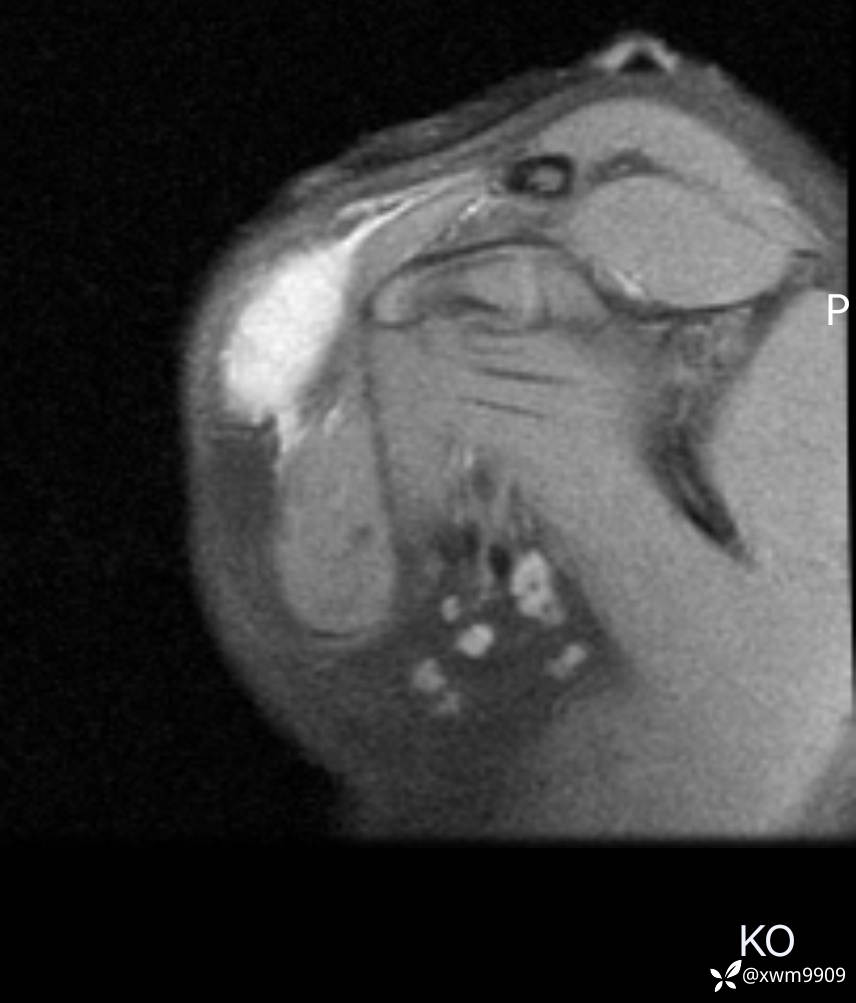

3、查体,右锁下方可及一约5x6Cm肿物,软丶边清丶未见明显发红,肤温不高,压痛明显,不可推动,稍有波动感。其他无特殊。

CT:

2、CT、MR肿块内可见液-液平面,常见有哪些疾病。

3、如何定性、定病?